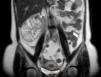

Renal ultrasound showed a well-defined mass in the lower pole of the right kidney. Renal magnetic resonance imaging was performed to clarify its nature and relations, which showed a well-defined, macronodular mass measuring 85mm at its widest point, with radial expression and a central necrotic scar with high contrast uptake, suggestive of renal oncocytoma (Figs. 1 and 2).